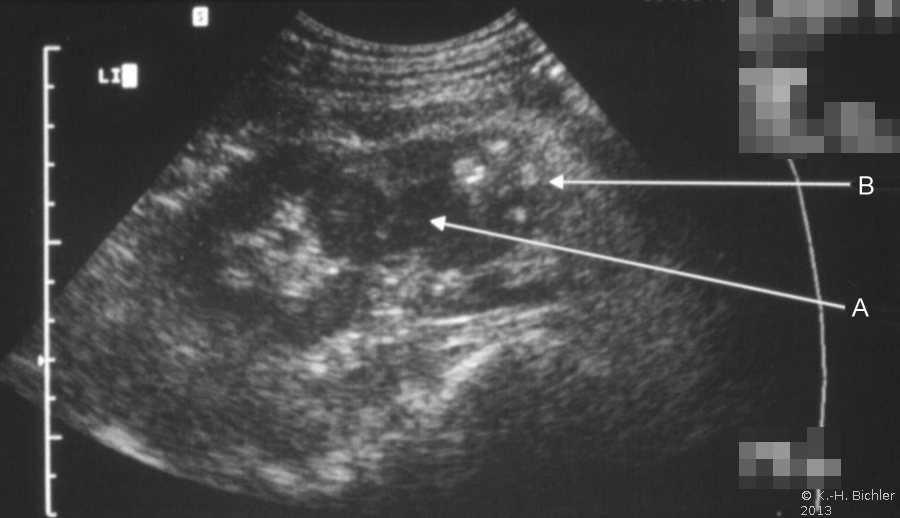

Papillennekrose

Sie tritt zumeist bei Patienten mit Diabetes Mellitus bzw. bei Harnwegsobstruktionen auf (Komplizierte Pyelonephritis). Dabei können eine oder alle Papillen befallen sein. Histologisch findet sich eine koagolative Infarktnekrose, d.h. die Umrisse von befallenen Tubuli sind erhalten. Leukozytäre Reaktionen finden sich an den Rändern der Nekrosebezirke Literatur:Robbins: "Pathologic Basis of Disease", Saunders Philadelphia, 1999.